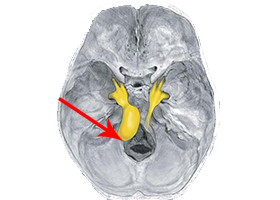

53歳女性、左舌咽神経痛

[画像所見]

-

頭部MRI -

頭部造影三次元CT

左後下小脳動脈が左舌咽神経を圧迫していたために左咽頭部を中心に激しい痛みが生じていました。